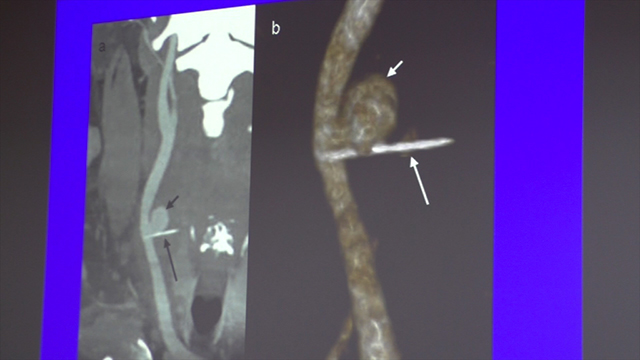

Un innovativo intervento chirurgico è stato eseguito con successo nella giornata di ieri su una paziente giunta al Pronto Soccorso del nosocomio beneventano con la “rottura...